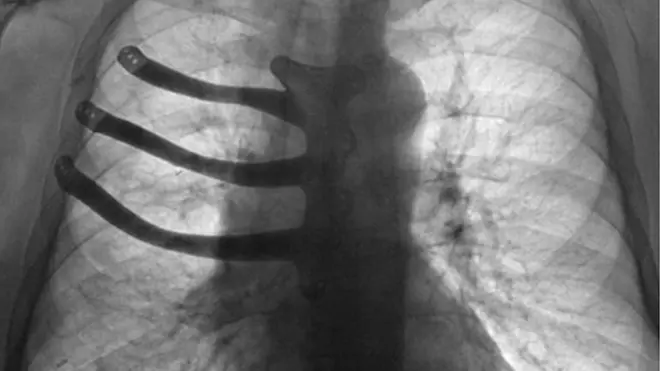

«Он [водитель] догнал нас сзади, он разговаривал по телефону, — рассказал Ричардс. — Мои два друга были сбиты с велосипедов, но отделались множественными переломами. Я, к сожалению, оказался зажатым под автомобилем, в результате чего получил сильные ожоги одной стороны тела и лица, а также травмы ребер с правой стороны».

Он продолжает посещать Бристольский медицинский центр, где ему только что установили протезы лица. С помощью технологий центра были изготовлены большой протез глазницы и шины для шрамов на шее.